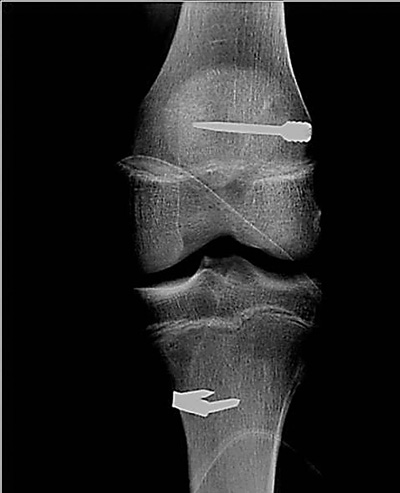

Por último nos parece importante mencionar que sin ser una indicación técnica precisa, el uso de este injerto es considerablemente más barato, lo que de alguna manera condiciona la elección cuando económicamente existen limitaciones. El otro injerto de amplia difusión y que en el último tiempo tiene un mayor número de adeptos es el de semitendinoso – gracilis (SMT-GRA) cuádruple; éste es de más fácil obtención, es de una técnica quirúrgica más simple y las características finales del injerto lo hacen parecer de mejor aspecto. El postoperatorio es menos doloroso y la reincorporación laboral es más rápida. Una de las principales ventajas es la preservación del aparato extensor (19). Debido a lo anterior la utilización de este injerto se ha hecho más popular en los últimos años. El injerto SMT-GRA, tiene escasa morbilidad del sitio donante (20). Se debe tener la especial precaución en la rehabilitación de evitar el trabajo intenso en la región posterior del muslo para evitar desgarros, que suelen ocurrir entre la tercera y la quinta semana de recuperación. Es fundamental la permanente observación, el conocimiento del equipo y el trabajo en conjunto con el kinesiólogo. El injerto suele ser de gran calidad, mantiene excelente vitalidad y permite una rehabilitación fácil, con poco dolor, múltiples trabajos muestran igual estabilidad que el HTH. Dentro de las desventajas que se han atribuido a este injerto podemos mencionar la menor resistencia. Esta se mejora con el empleo de un injerto cuádruple, llegando a una resistencia de 4090 N y una rigidez de 776 N/mm (21). El Injerto cuádruple se em-plea normalmente salvo alguna falla en la extracción que está determinada por la experiencia del cirujano, falla de instrumental del tendon-stripper, mala calidad o mínimo grosor de los injertos. Otra de las desventajas de este tipo de injerto es la menor resistencia en la fijación, integración más lenta y mayor elongación; lo que guarda relación con el método de fijación de la mayoría de los de tejidos blandos. A nuestro parecer los tipo cross - pin, son mejores al no estar externos, son más proximales evitando el efecto bungee y limpiaparabrisas, para disminuir este efecto es bueno dilatar los túneles, las paredes del túnel se compactan y con esto se obtiene mejor fijación (19). Es útil también, pretensar el injerto sobre todo en casos de mayor laxitud. Nosotros consideramos que en pacientes con esqueleto inmaduro con rotura del LCA la indicación es utilizar injerto de SMT-GRA. La frecuencia de lesiones de LCA en pacientes con esqueleto inmaduro cada día se incrementa, debido al aumento de la práctica deportiva competitiva a edades más precoces. Hemos realizado más de 100 cirugías de reconstrucción de LCA en menores con cartílago abierto. (Fig. 3). Preferimos no utilizar en este grupo etáreo aloinjertos debido a la mayor frecuencia de riesgo de enfermedad tumoral ósea.

![]() |

| Figura 3: Reconstrucción de LCA en paciente con cartílago abierto. |